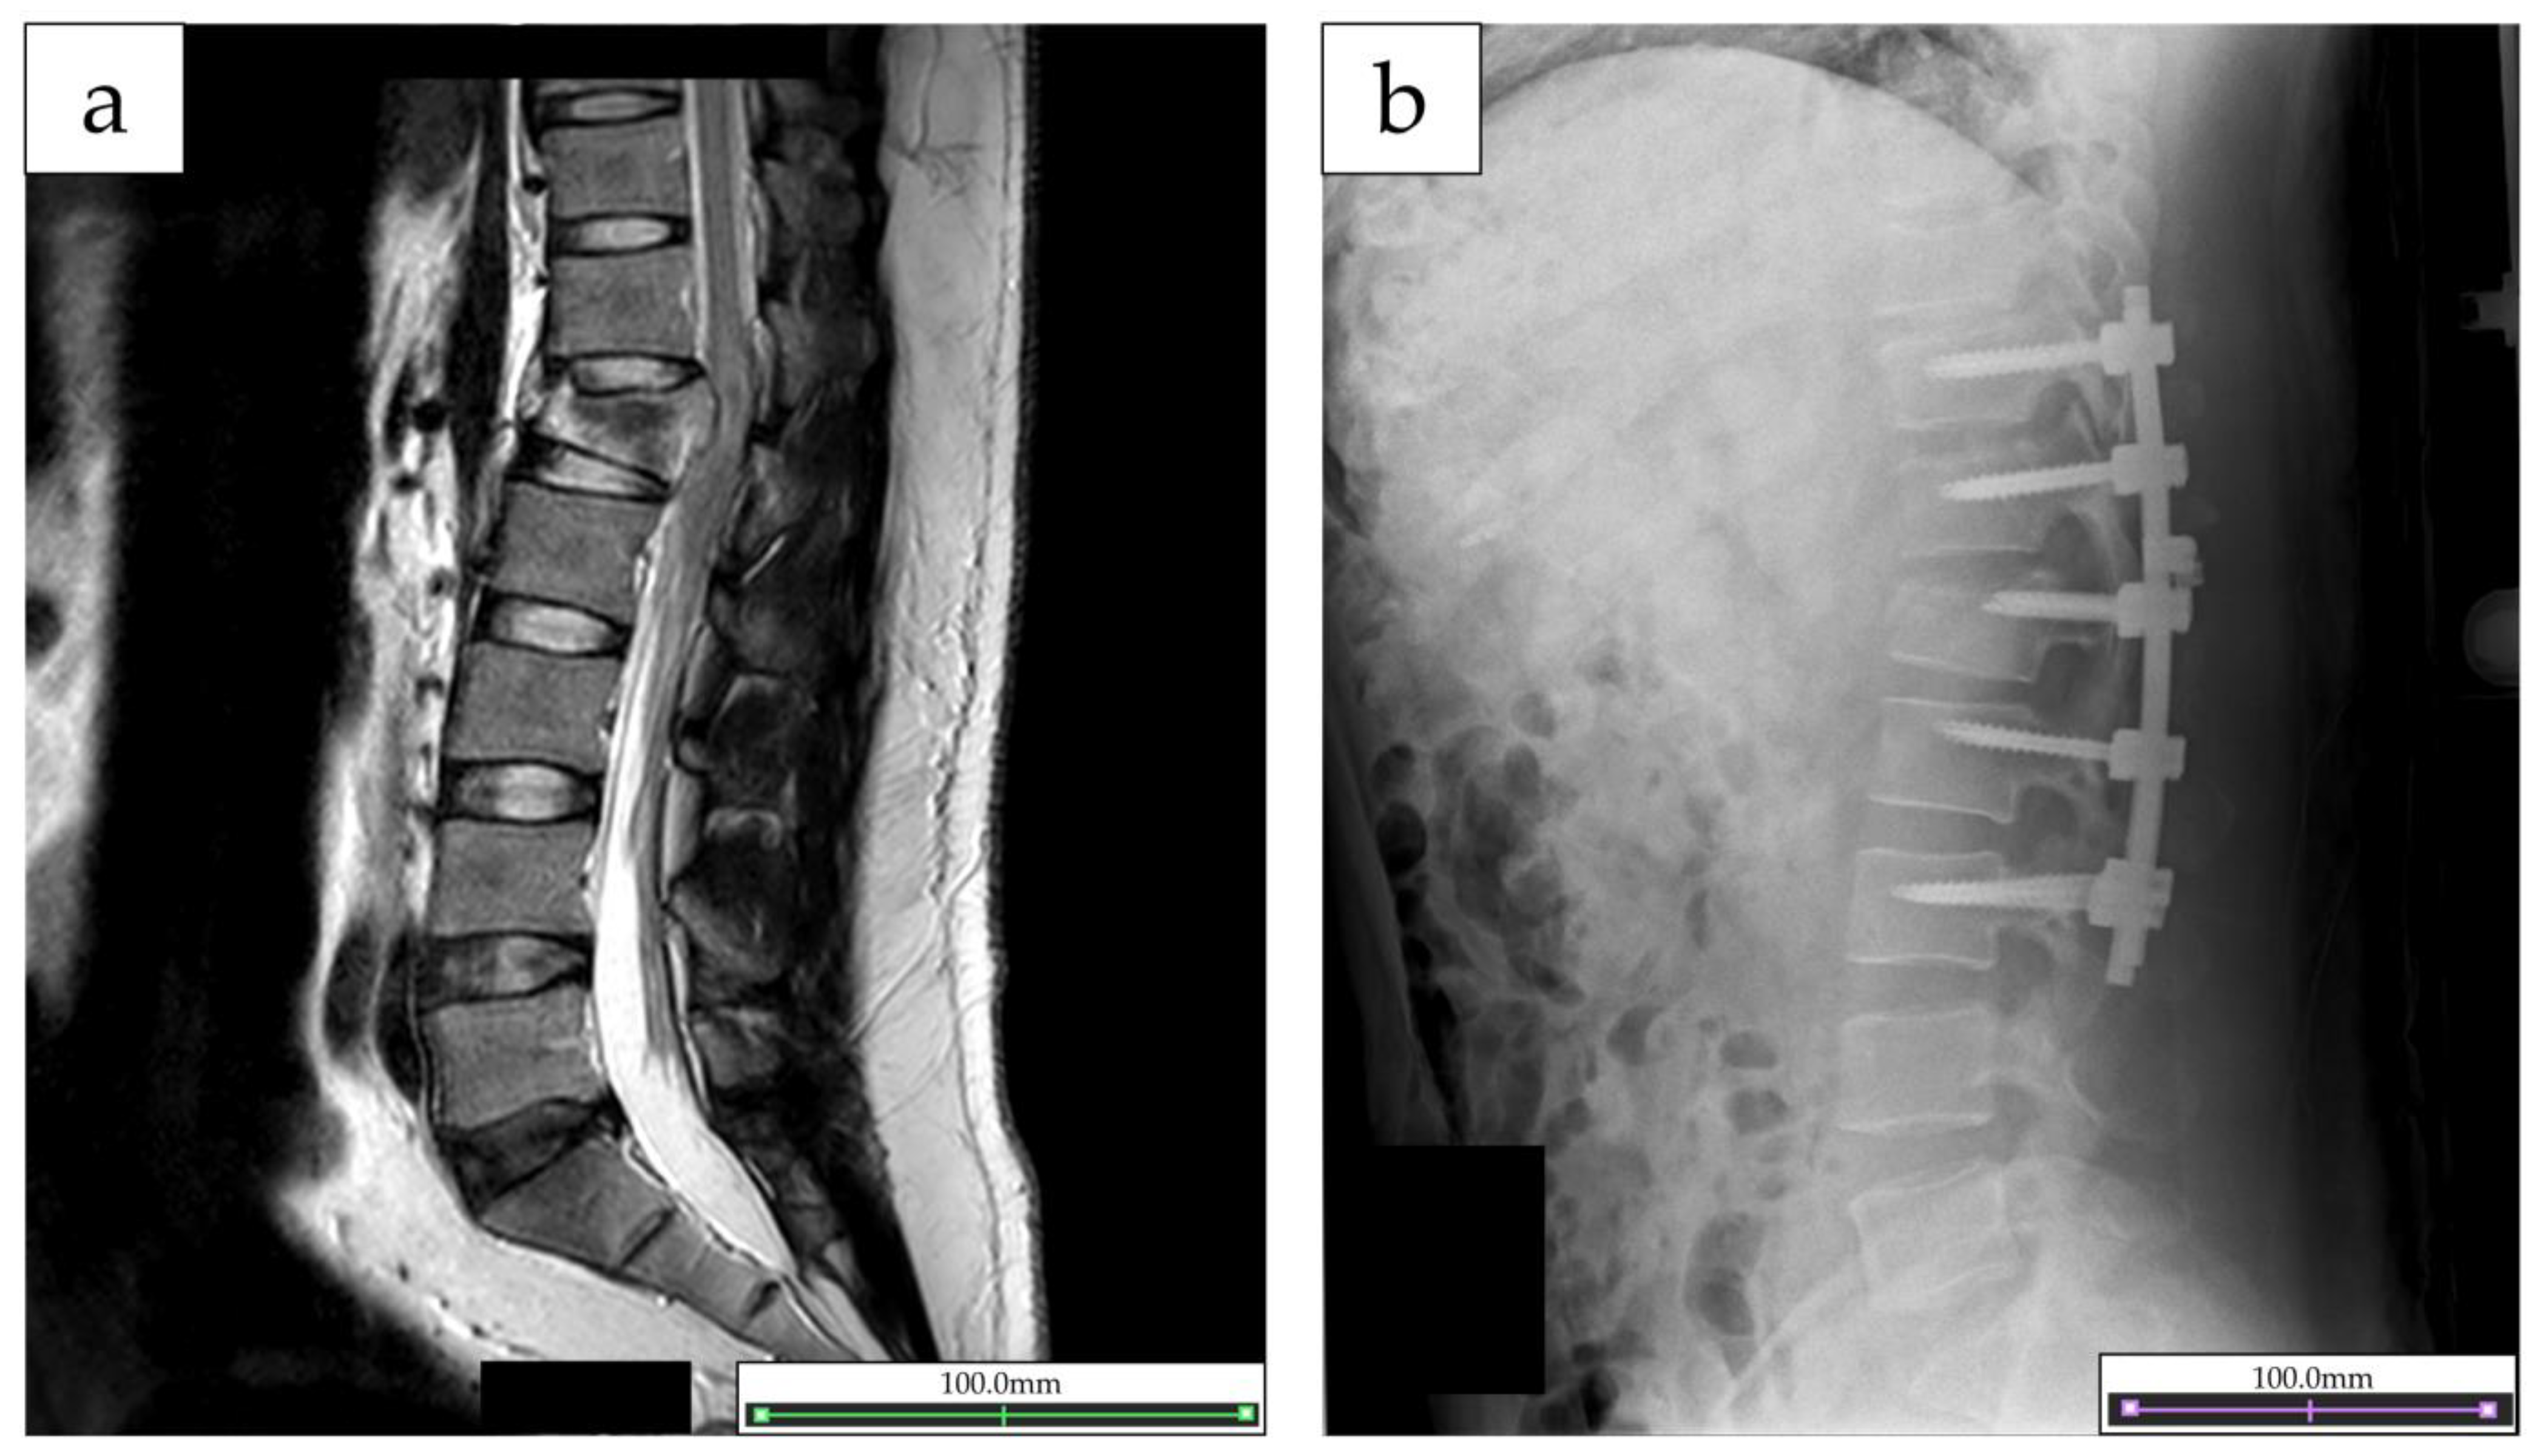

2.1. Participant